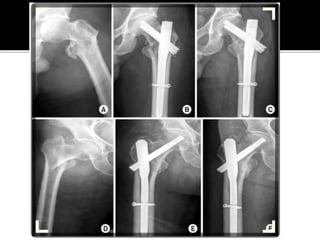

Failed

Subtrochanteric

fracture fixation

with broken DCS

and plate

After 51 days